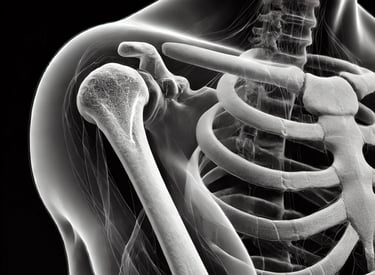

Implantes en titanio trabecular

Impresión 3D en titanio grado médico: asistencia al cirujano y ortopedia desde las imágenes tomográficas hasta la impresión final